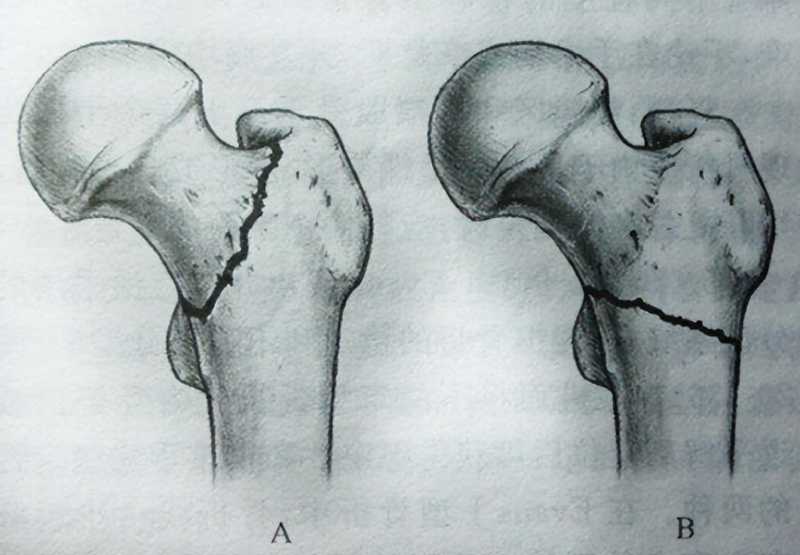

第四名:股骨骨折

被排名第四位的是股骨骨折。

提到骨折,任何一根骨头骨折都让人难以招架,更何况是你体内最粗壮、最坚固的骨头——股骨骨折。

人的股骨是下肢主要负重骨之一。

再加上沿着腿部延伸的所有大动脉,如果不幸股骨骨折,这骨折会占人体全身骨折的4%-6%,那真的要痛不欲生。

股骨骨折一般是因为,某种严重事故(例如运动损伤或车祸)引起的,当该区域骨折时,碰到一点儿都会立即让人们尖叫。

老年人也是股骨骨折的高发人群。

这主要是由于老年人的骨矿物质密度降低,从而导致骨折易感性增加。并且髋周肌群退化,反应能力下降,无法减轻或抵消外来压力而造成的。